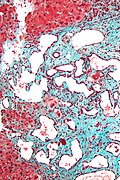

Image:Cirrhosis_high_mag.jpg | Cirrhotic liver - trichrome stain. (WC/Nephron)

• Trichrome - to detect fibrosis/cirrhosis.

• Mallory trichrome: red = hepatocytes, blue/black = nuclei, green = fibrosis.